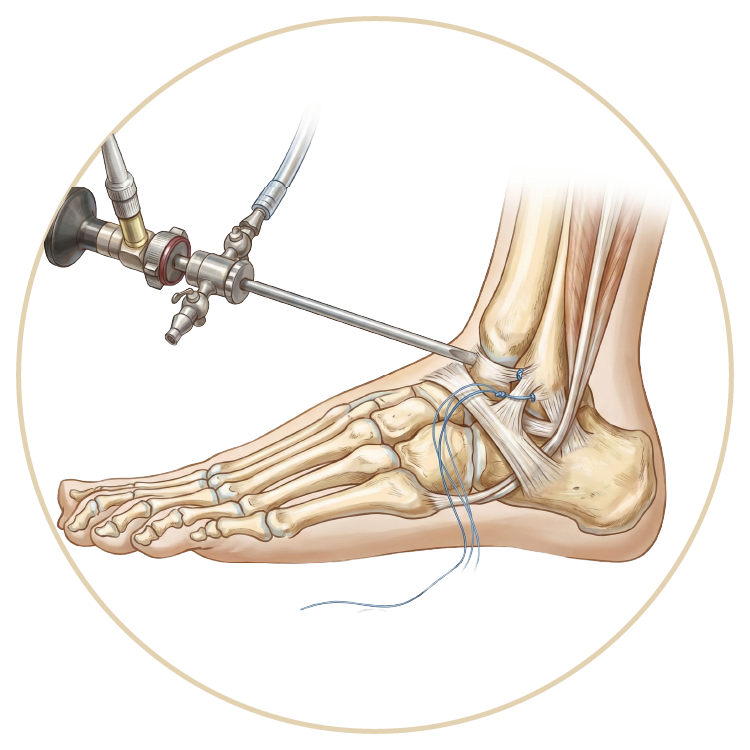

Ayak Bileği Yaralanmaları

Ayak Bileği Artroskopisi